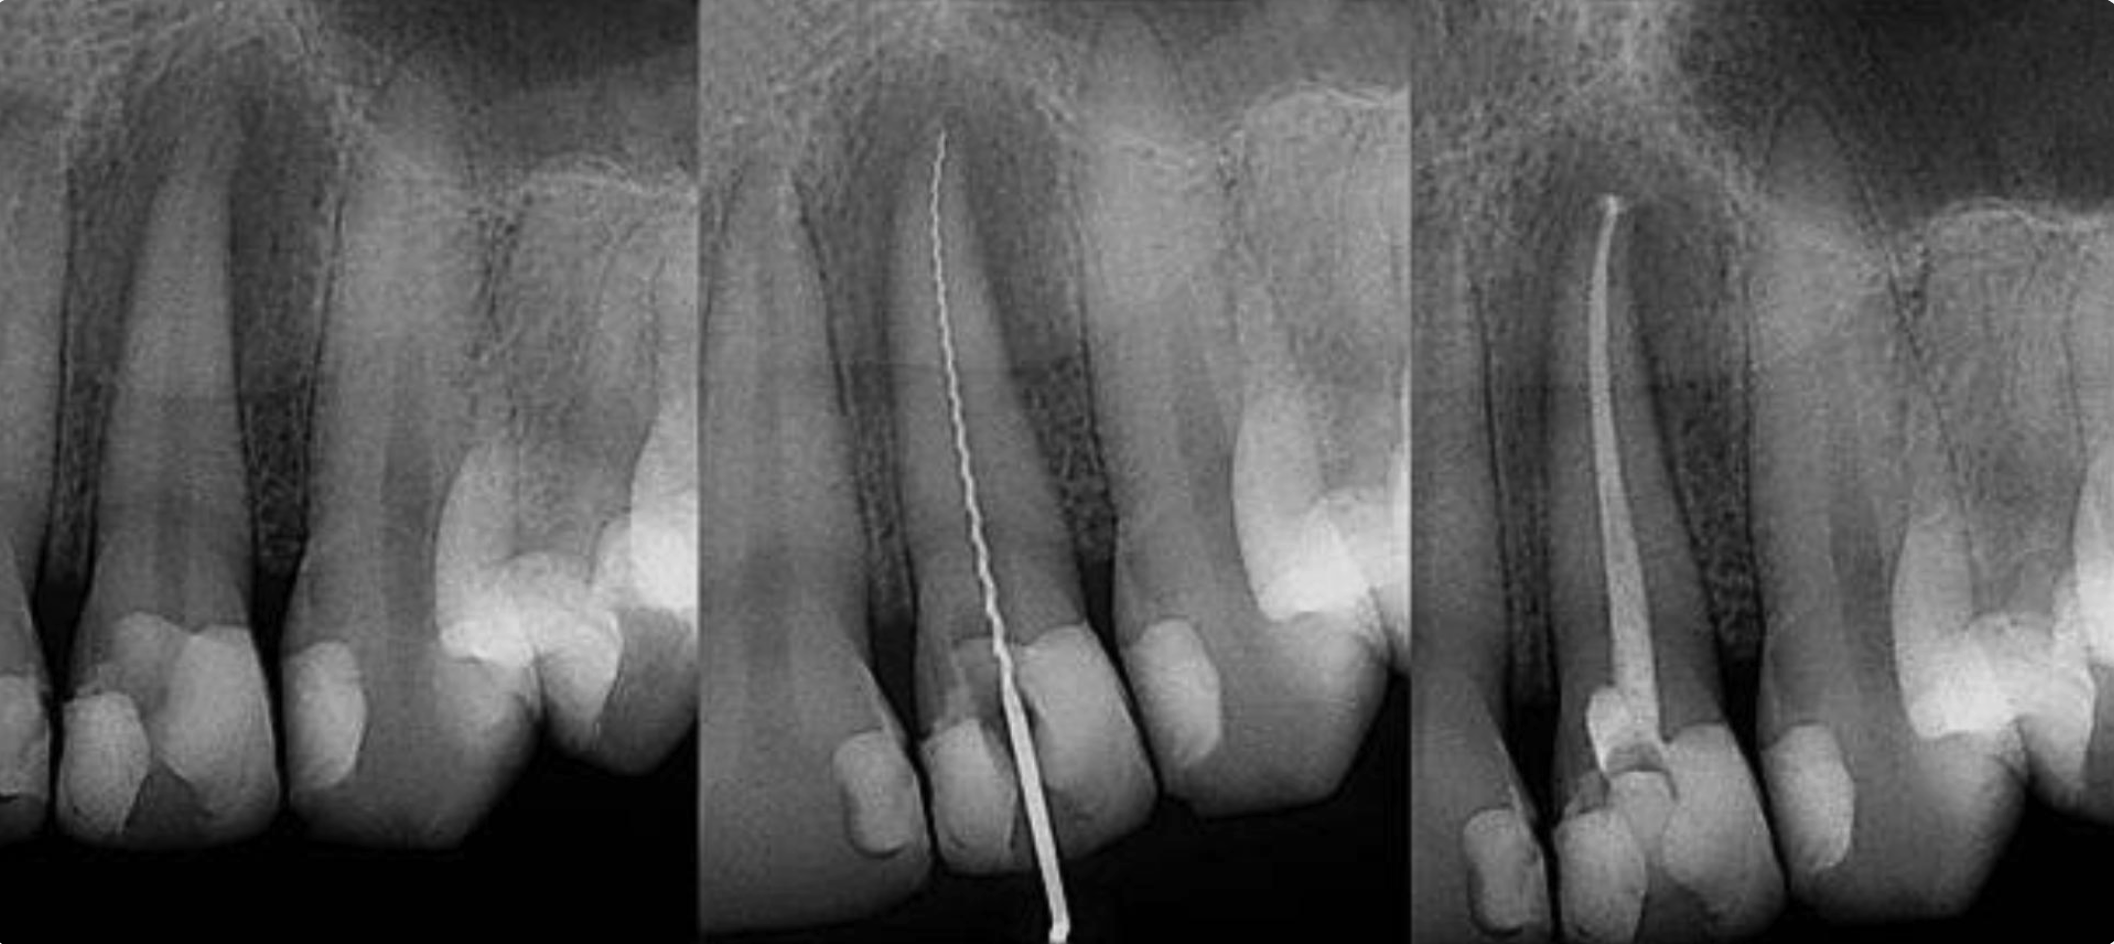

Root canal treatment involves one to three visits during which your endodontist removes the affected tissue. After the tissue is removed, the interior of the tooth will be cleaned and sealed.

Finally, the tooth is filled with a temporary restoration.   You will need to make an appointment with your General Dentist to have the tooth permanently restored.   If your tooth had extensive decay, your doctor may suggest placing a crown to strengthen and protect the tooth from breakage. As long as you continue to care for your teeth and gums with regular brushing, flossing, and checkups, your restored tooth can last a lifetime.

Retreatment Procedure

First, Dr. Tayebaty will discuss your treatment options. If you choose retreatment, he will reopen your tooth to gain access to the root canal filling material. Removal of restoration and filling material allows access to the infected canals.

After removing the root canal filling, the endodontist can clean the canals and carefully examine the inside of your tooth using magnification and illumination, searching for any additional canals, possible fractures or unusual anatomy that requires treatment.

Your endodontist will clean the canals, seal them, and place a filling in the tooth. If the canals are unusually narrow or blocked, your endodontist may recommend endodontic surgery.